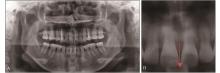

图 3

术前X线片检查A:全景片;B:箭头示11、21牙槽嵴顶至21牙切端垂直距离约12.36 mm。"